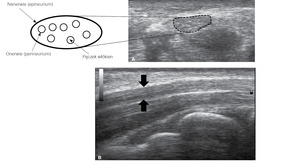

Nerwy obwodowe uwidacznia się w przekroju poprzecznym i podłużnym.1-3 W przekroju poprzecznym nerw ma owalny elipsoidalny lub bardziej spłaszczony i nieregularny zarys oraz charakterystyczną siatkowatą strukturę, która wiąże się z obecnością pęczków włókien nerwowych (aksonów), otoczonych hiperechogennym onerwiem (perineurium). Delikatna tkanka, która oddziela od siebie poszczególne aksony w pęczku (śródnerwie, endoneurium) w obrazie USG wysokiej rozdzielczości jest hipoechogenna. Nerw otoczony jest grubszą błoną – nanerwiem (epineurium), łatwą do uwidocznienia na obrazie ultrasonograficznym, na którym jest hiperechogeniczna. W przekroju podłużnym wyraźne hiperechogenne, równolegle położone linie wyznaczają nanerwie. Między nimi znajdują się równoległe linie o nieco mniejszej echogeniczności, które odpowiadają poszczególnym pęczkom włókien w obrębie nerwu (ryc. 1). Mięśnie charakteryzują się nieco mniejszą, a ścięgna – nieznacznie większą echogenicznością od nerwu.